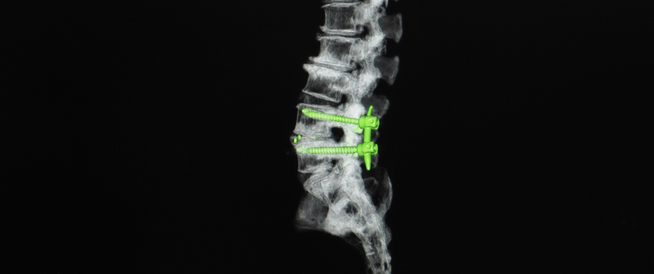

سماحة وجه فراس تخفي قهرا تذرفه شفاهه المرتجفة أثناء طلبه بعفة المساعدة والعون في معاناته بانزلاق غضروفي قطني في الفقرة الرابعة والخامسة .

حال وقوفه وسيره جدا سيء وبعد النظر للتقارير فإنه يحتاج إلى تدخل طبي لاستئصال الغضروف وتثبيت الفقرة القطنية والعجزية .